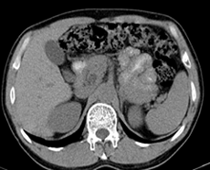

患者,男,57,常年不吃午饭,近一个月来腹部隐痛,无明显黄疸,明天进行增强扫描,图象另上传,麻烦各位帮忙一起看看讨论讨论

肝外胆管扩张,胰头增大,肠系膜上静脉似有包埋征象。

考虑:胰头占位性病变,建议增强进一步检查。

肝内外胆管扩张,胆管未端阻塞,建议mri检查

肝外胆管稍扩张,胰腺钩突略增大,但外形尚可,境界清楚。(常年不吃午饭)提示胰腺炎可能大,肿瘤第二步考虑。

胰头增大,胆总管增宽,考虑胰头癌可能性大,明天看增强片有助诊断.